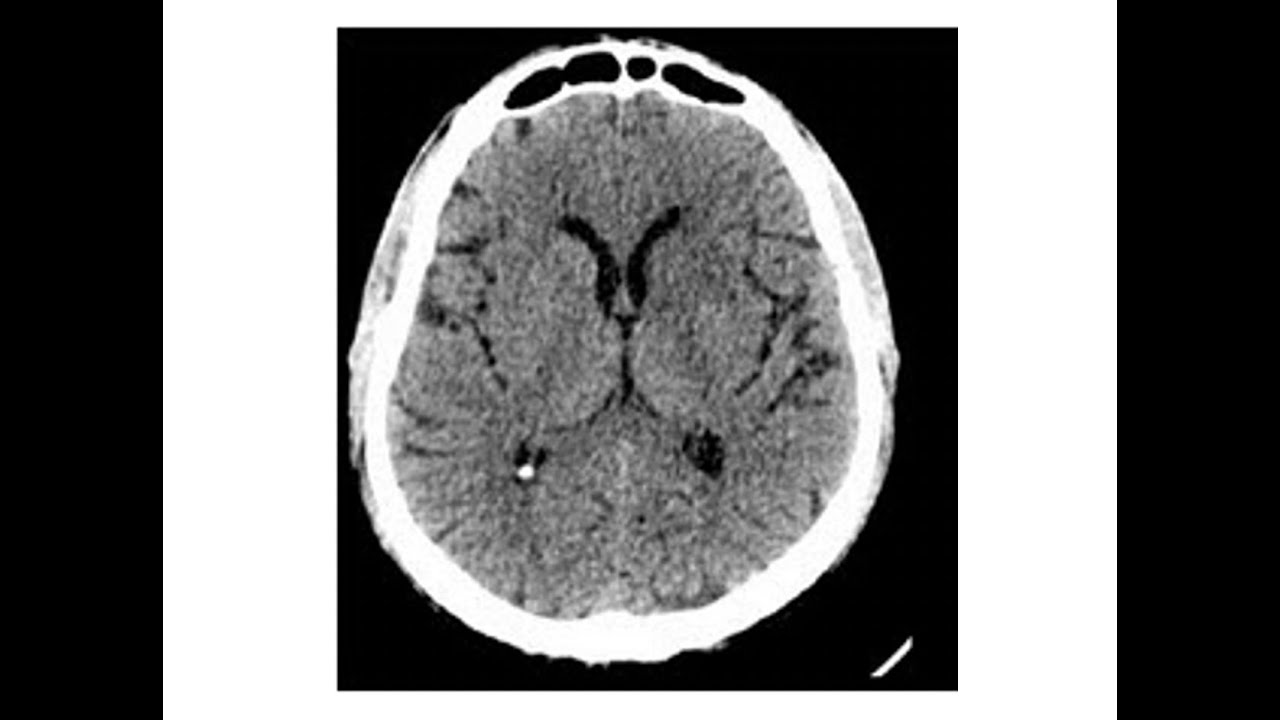

chamadas cornos isso mesmo que você ouviu cornos chifres pontas esses cornos são os cornos que você ostenta por aí andando pela rua eu ostento os meus com orgul porque os ventrículos laterais eles apresentam três cornos cada um deles portanto eu fico andando por aí com seis cornos na minha cabeça além dos ventrículos laterais nós temos também o terceiro ventrículo que fica Centralizado e depois nós temos o quarto ventrículo que você pode ver na imagem aqui do lado que a gente consegue identificar os ventrículos laterais como esses dois azuis que você está enxergando aí o terceiro

ventrículo é aquele amelinho ali no meio e o quarto ventrículo é aquele que tem roxinho embaixo na imagem tá vendo ali Esses são os ventrículos que estão dentro do nosso encéfalo então agora vamos observar esses ventrículos Este é o corno anterior do ventrículo lateral o corno anterior do ventrículo lateral dá origem ao corpo e o corpo vai dar origem ao corno posterior que fica lá no lobo occipital do corno posterior temos o corno IOR que fica bem lá no lobo temporal Nós temos dois ventrículos laterais um direito e outro esquerdo que vai aparecer aqui agora

lá em cinza mais claro os dois ventrículos laterais vão se comunicar pelos forames ventriculares e se comunicam com o terceiro ventrículo que é que você tá vendo aí agora olha só os forames interventriculares que vão comunicar esses ventrículos veja que o terceiro ventrículo tem um orif íc que é onde há a aderência intertalâmica a aderência intertalâmica comunica os dois tálamos e um pouco mais inferior aqui nessa parte nós temos o terceiro ventrículo e do terceiro ventrículo Onde fica o hipotálamo aí o terceiro ventrículo se comunica inferiormente pelo Aqueduto cerebral que é esse que eu tô

mostrando aqui agora e O Aqueduto cerebral termina no quarto ventrículo o quarto ventrículo poru vez ele continua no canal central da medula por a medula fica logo abaixo do tronco encefálico Então ele continua no canal central da medula ali e vai se abrir lá no finalzinho olha aqui as imagens olha os ventrículos laterais em cinza um pouco mais claro ou branco o terceiro ventrículo o quarto ventrículo aqui mais ínfero posterior e a gente consegue ver a comunicação do Aqueduto cerebral e o canal central da medula espinal aqui a a aderência intertalâmica e aqui os forames